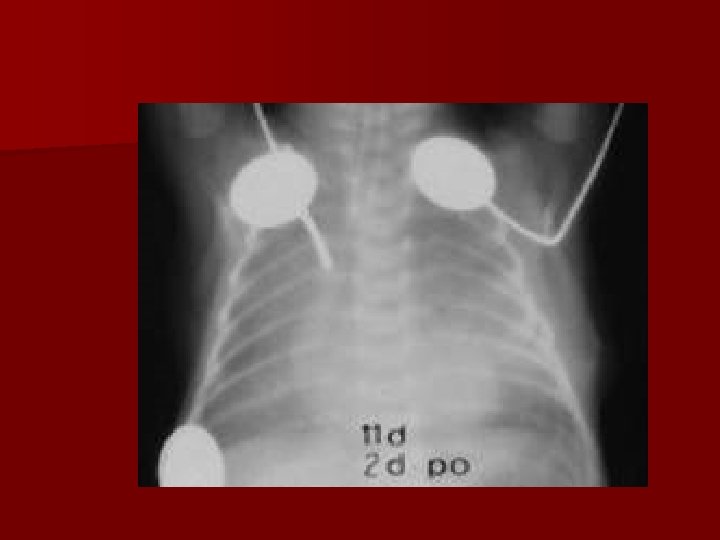

Przetoka przełykowo-tchawica (Tracheoesophageal fistula – TOF) 1: 3500 żywych urodzeń n Objawy uzależnione od typu TOF n TOF z atrezją przełyku – wcześniactwo – 25%, wady wrodzone – serca, z. Downa, wodonercze, atrezja XII, tracheomalacja, 10% niedrożny odbyt, 50% wady kręgów n

Przetoka przełykowotchawicza Tracheoesophageal fistula – TOF